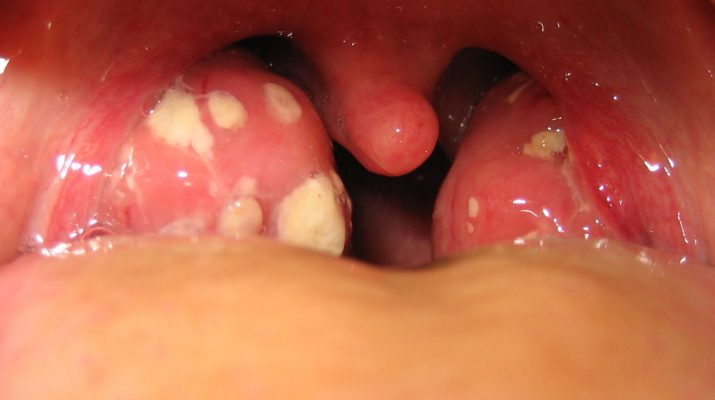

La mayoría de las personas han padecido alguna vez en sus vidas la amigdalitis. Este molesto padecimiento, esto es un tipo de infección que se produce a través de la inflamación de las amígdalas provocadas por una infección. Estas amígdalas se inflaman y en algunos casos, se pueden observar unos puntos blancos con pus. Sus síntomas más característicos además de los ya mencionados, son fiebre, falta de apetito, ronquera y en algunos casos, dolor de oído.